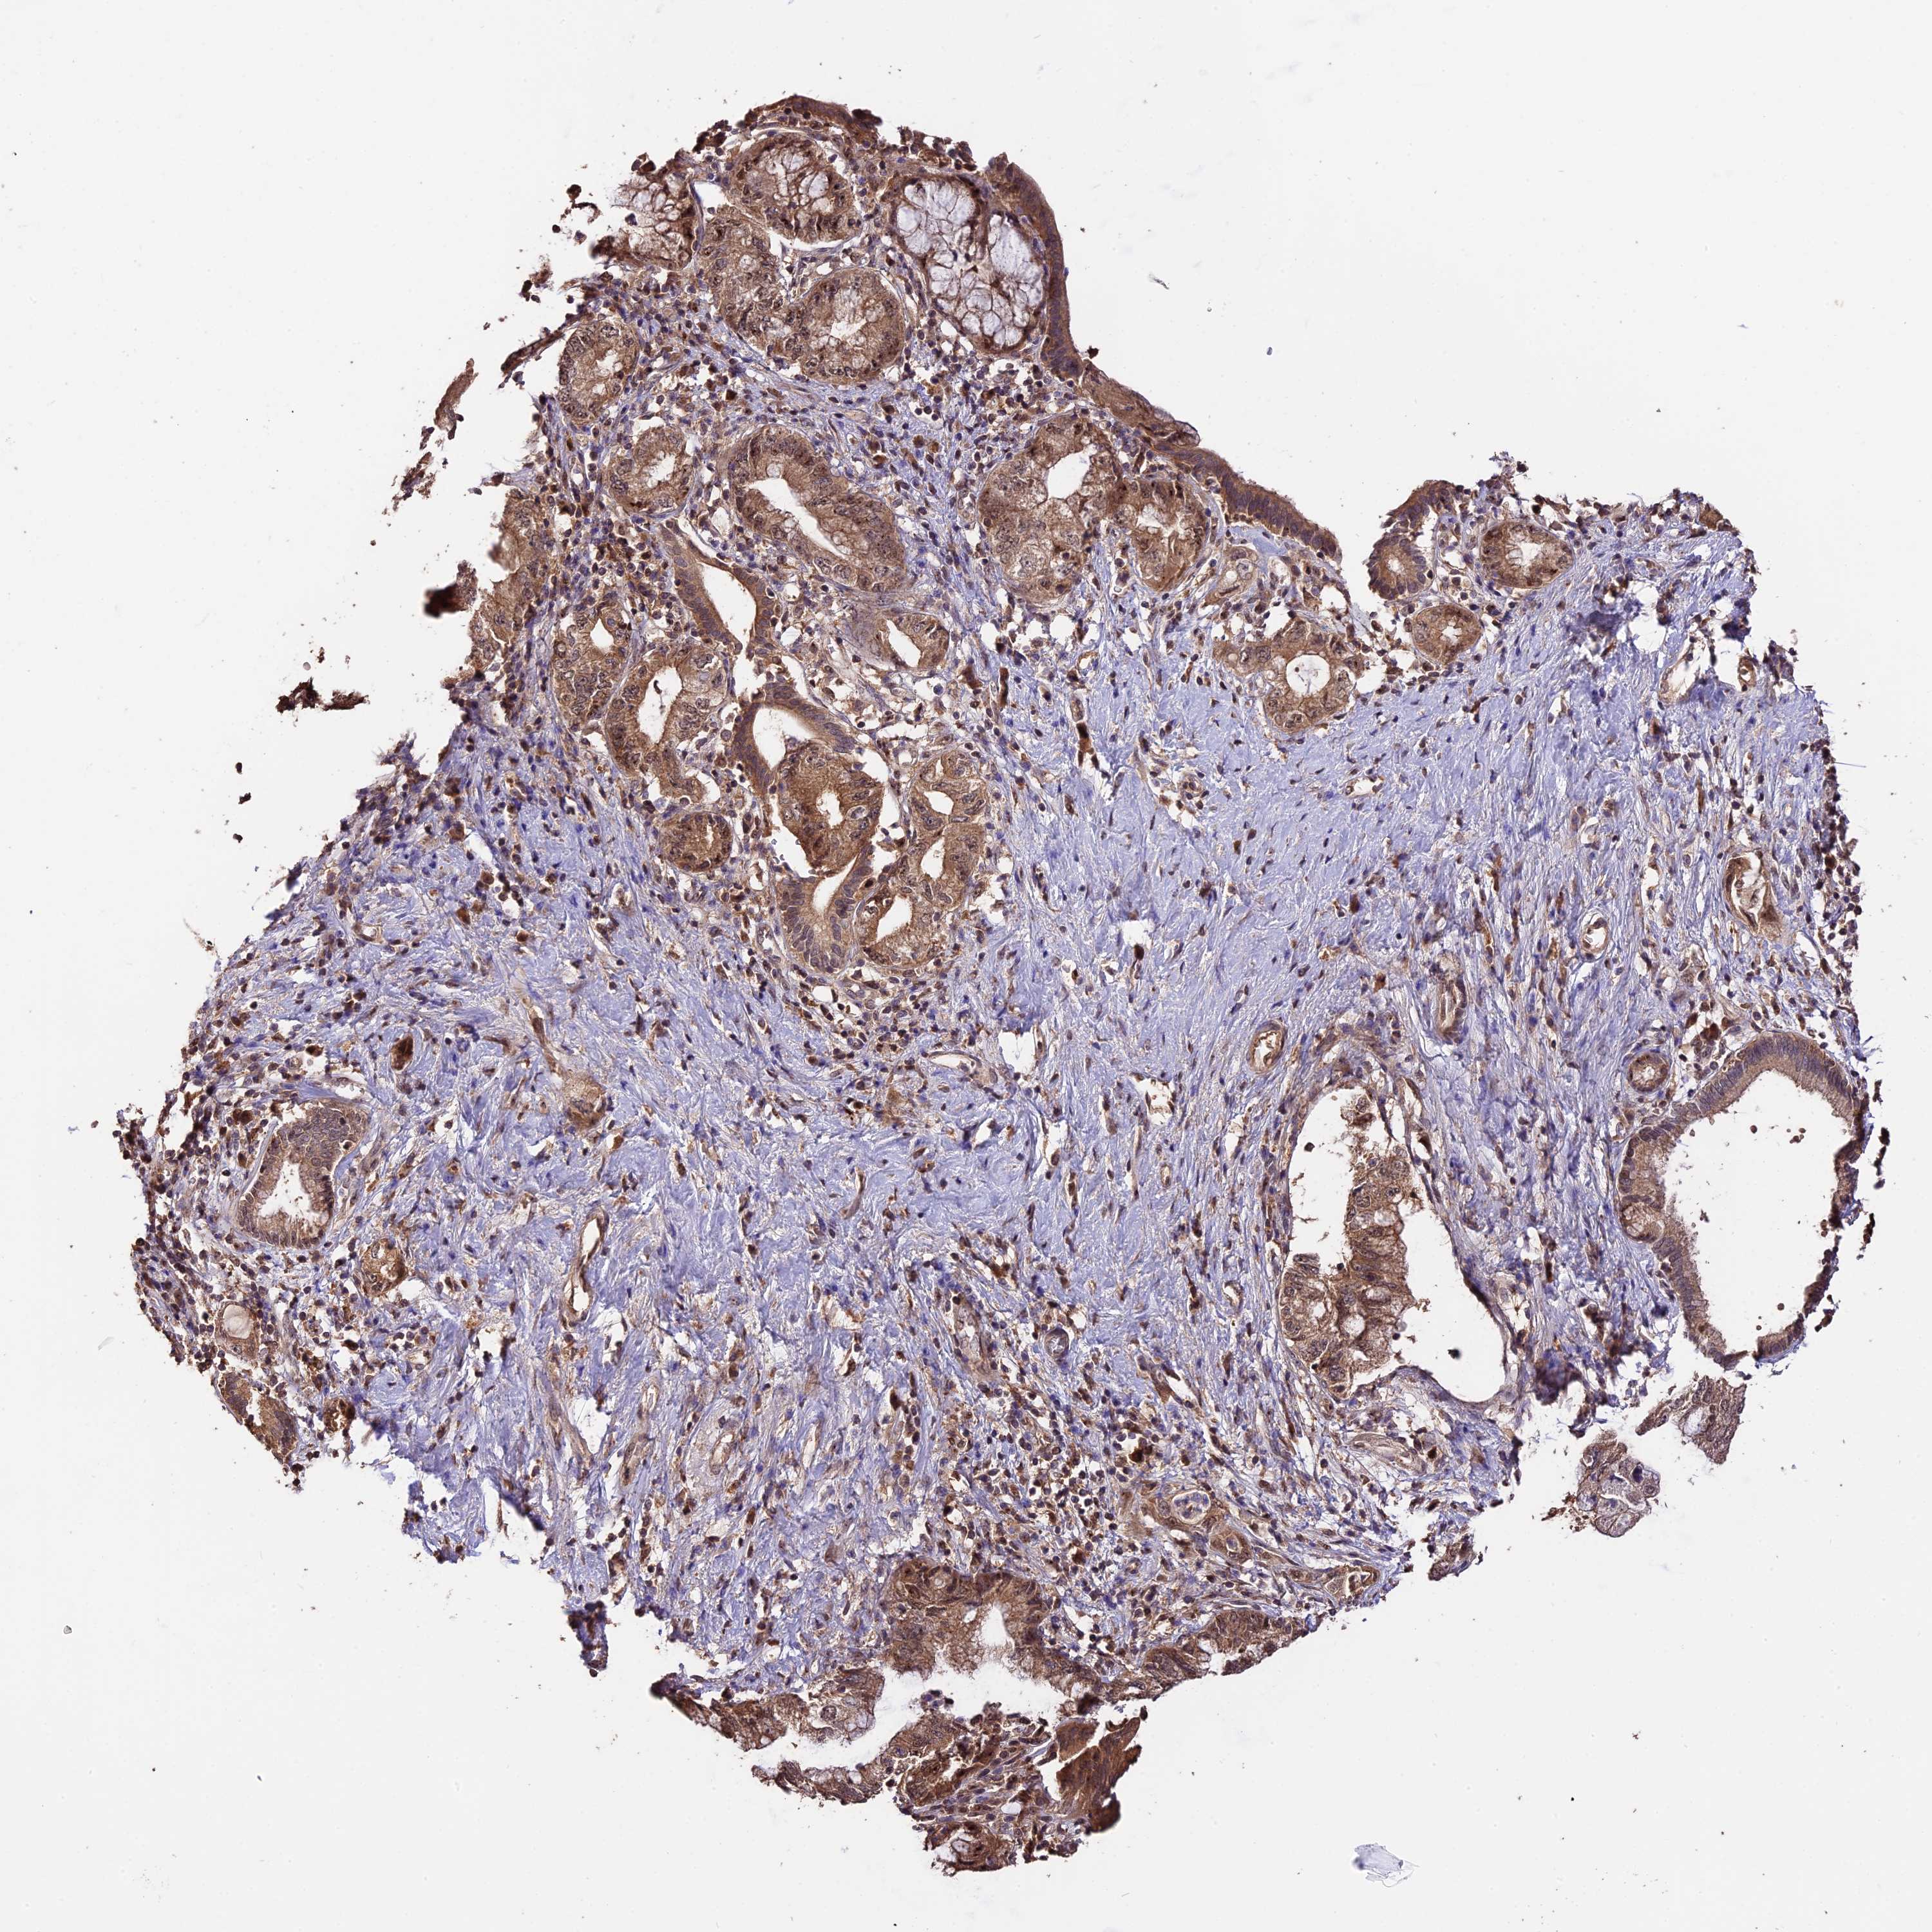

PANCREATIC CANCER - Protein expressioni

A mouse-over function shows sample information and annotation data. Click on an image to view it in a full screen mode. Samples can be filtered based on level of antibody staining by selecting one or several of the following categories: high, medium, low and not detected. The assay and annotation is described here.

Note that samples used for immunohistochemistry by the Human Protein Atlas do not correspond to samples in the TCGA dataset.

Antibody stainingi

Antibody staining in the annotated cell types in the current human tissue is reported as not detected, low, medium, or high, based on conventional immunohistochemistry profiling in selected tissues. This score is based on the combination of the staining intensity and fraction of stained cells.

Each image is clickable and will lead to virtual microscopy that enables deeper exploration of all samples and also displays staining intensity scores, fraction scores and subcellular localization as well as patient and tissue information for each sample.

Antibody HPA041130

Antibody HPA041380

Staining

High

Medium

Low

Not detected

Intensity

Strong

Moderate

Weak

Negative

Quantity

>75%

75%-25%

<25%

None

Location

Nuclear

Cytoplasmic/membranous

Cytoplasmic/membranous,nuclear

Adenocarcinoma, NOS